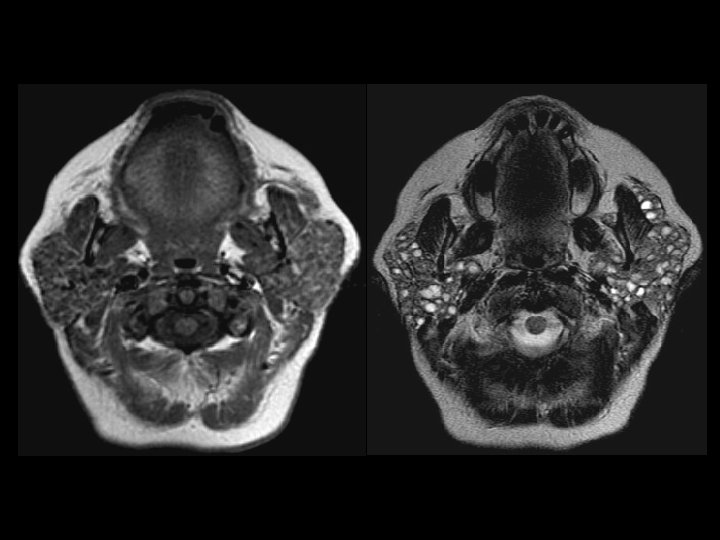

Lymphoepithelial cysts in HIV • Findings: – Enlarged parotid glands containing innumerable small cystic lesions • Manifestation in HIV, unclear etiology • Soft, non-tender enlarged glands • ddx: – Sjogren’s syndrome – Warthin’s tumors